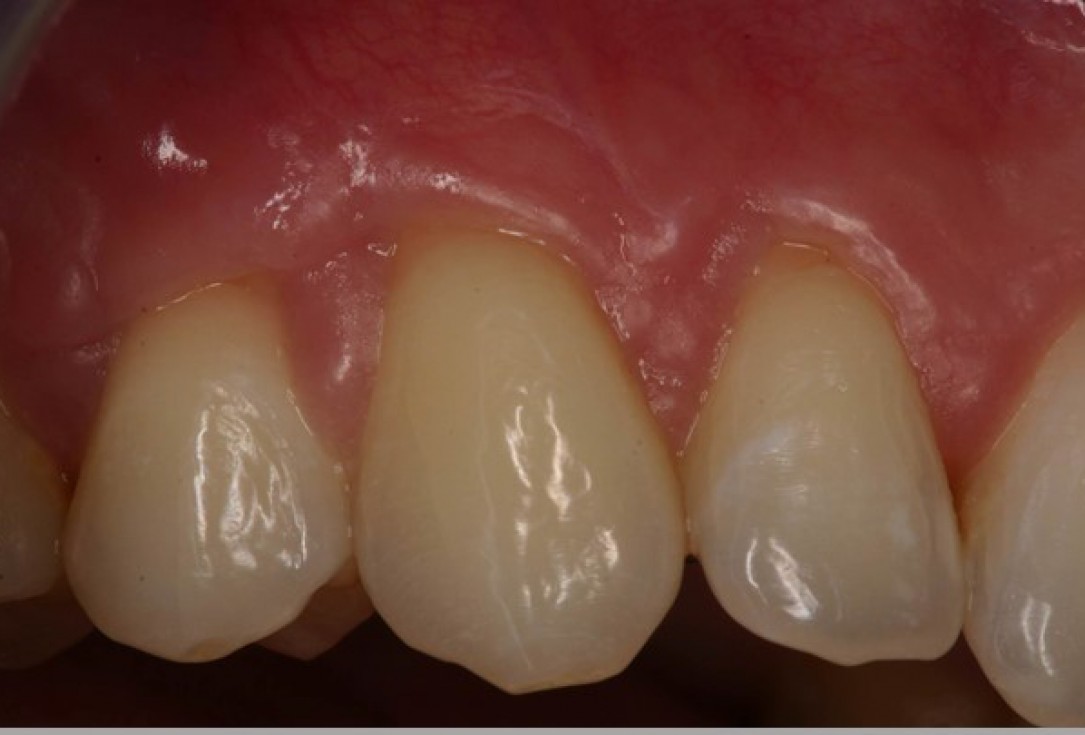

05/06 - Clinical situation 3 months post-operative. Significant coverage of the roots and increased thickness of the marginal tissue.Multiple gingival recessions treated with the modified coronally advanced flap in conjunction with mucoderm® - Prof. Dr. Dr. A. Kasaj